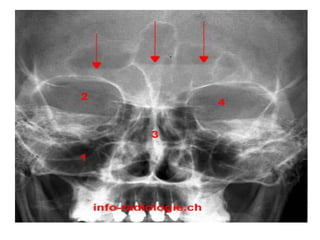

Le document décrit l'anatomie des sinus et des fosses nasales, incluant deux fosses nasales et quatre sinus faciaux. Il explique le drainage des sinus dans les fosses nasales via des ostiums naturels, précisant leur localisation dans les méats moyen et supérieur ainsi que dans la gouttière sphéno-ethmoïdale. Des explorations radiologiques, telles que la tomodensitométrie, sont mentionnées pour évaluer les sinusites.